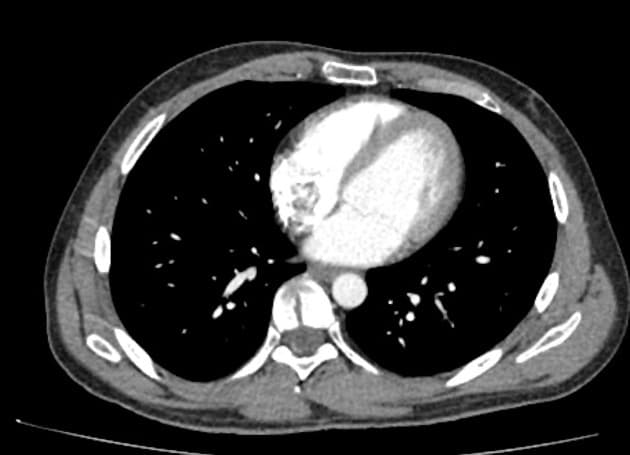

Đã biết hội chứng Von Hippel-Lindau (VHL). Đang sàng lọc các khối u thận. Bệnh nhân có bàng quang thần kinh. Chụp cộng hưởng từ (MRI) được thực hiện nhằm giảm phơi nhiễm tia phóng xạ.

- Nhiều nang thận đơn thuần cũng như nhiều u thận tổn thương hỗn hợp đặc - nang.

- Tuyến tụy cũng chứa một số lượng rất lớn các nang rải rác khắp nơi.

Ca lâm sàng này biểu hiện đầy đủ các đặc điểm của hội chứng Von Hippel-Lindau (VHL), bao gồm nhiều nang thận đơn thuần và nhiều u thận tổn thương hỗn hợp đặc - nang. Tuyến tụy cũng có rất nhiều nang lan tỏa.

Bệnh nhân đã từng được phẫu thuật cắt bỏ u mạch thần kinh đệm (hemangioblastoma) ở tủy sống, gây ra tình trạng bàng quang thần kinh (lưu ý hình ảnh cắt lớp ngang T2 cho thấy dấu hiệu của phẫu thuật cắt mảnh cung (laminectomy) vùng ngực và các thay đổi tại tủy sống).